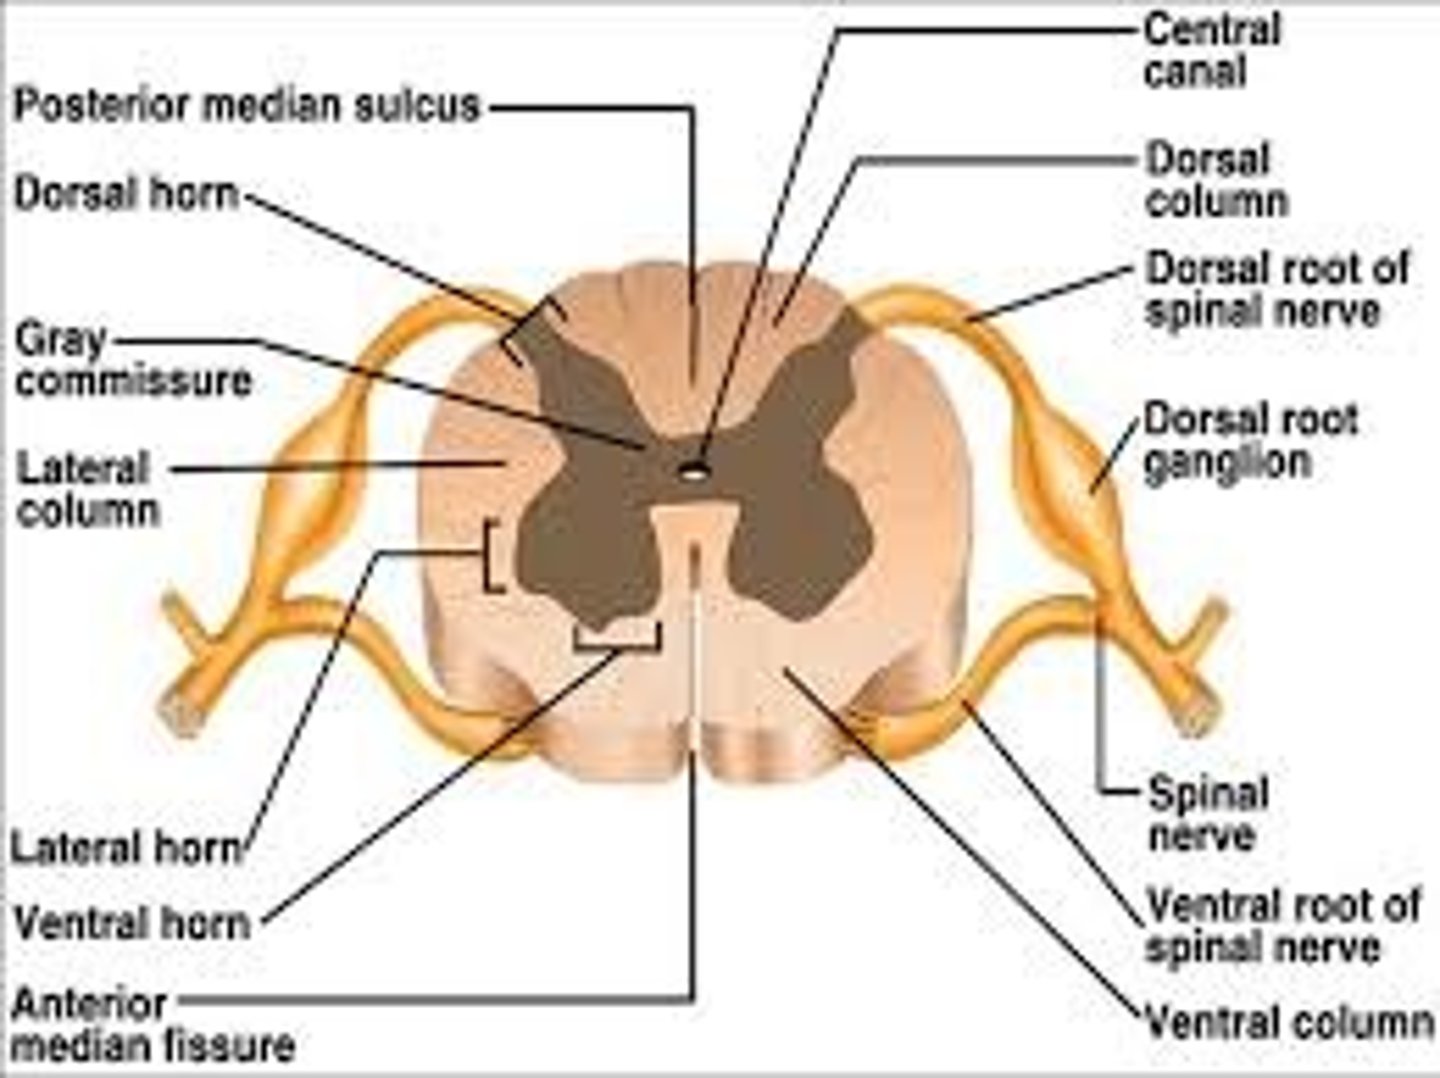

Spinal cord Anatomy (cross-sectional)

1)Internal butterfly shaped gray matter,

2)Exterior white matter,

3)Central canal filled with cerebrospinal fluid (CSF),

4)Cushioned & protected by meninges,

5)Pia mater,

6)Spinal nerves leave at the level of each vertenrae

Horns of Spinal Cord Anatomy

Dorsal Horns,

Ventral Horns,

Lateral Horns

Dorsal Horns

Lateral Horns

Ventral Horns

Interneurons

exterior white matter of the spinal cord

Ascending (sensory) and descending (motor) myelinated nerve tracts,

Posterior, anterior, lateral columns or funiculi

Posterior Columns

Anterior Columns

Lateral Columns/ funiculi

Central canal filled with what?

Central canal filled with cerebrospinal fluid (CSF)

Cushioned and protected by meninges

1) Cover the spinal cord

2) Dura mater, Arachnoid & Pia mater

dura mater of spinal cord

1) Separated from the periosteum by the epidermal space (fat, blood vessels)

2) Subdural space between dura and arachnoid mater

Dura Mater